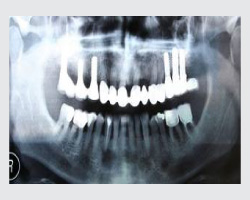

Dental implants are artificial tooth roots made of medical-grade titanium that are surgically placed into the jawbone. Once the implant integrates with the bone, a crown is fixed on top, giving you a strong, natural-looking replacement tooth.